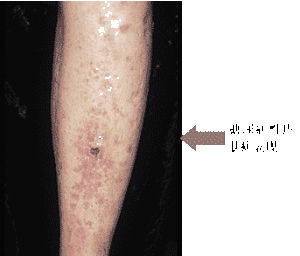

可發生於任何年齡但以青壯年為多見,平均發病年齡為30~40歲,兒童和新生兒罕見。伴有糖尿病者其發病年齡要比無糖尿病者早。性別差異明顯,男女比例約為1∶4。本病在東方民族和黑人中少見。皮損主要位於小腿側面,初起為圓形、堅硬、暗紅色無症狀的丘疹或斑塊一片或幾片不等,緩慢發展可相互融合成匐行性、卵圓形或不規則形,邊緣明確而不規則的堅硬斑塊。常呈棕紅色或紫色中央扁平或凹陷,表面光滑呈玻璃狀,有明顯的毛細血管擴張和纖維化,外觀如硬皮病樣,約1/3的皮損可能發生潰瘍。其周圍皮膚正常。損害位於深部者常呈結節狀,其表麵皮膚多無改變。損害尚可累及股、踝小腿屈側和足部,約15%發生在手臂、軀幹和頭皮個別病例下肢不受累。發生於頭皮者可因萎縮和瘢痕樣皮損而致禿髮,發緣處常有色素減退。病程為慢性經過,常緩慢發展達數年之久,也可長期處於靜止狀態或愈後形成瘢痕。